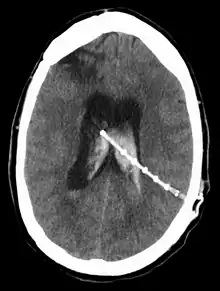

A ventriculoperitoneal shunt running from a brain ventricle to the abdominal cavity. CT scan of the head, 2016.